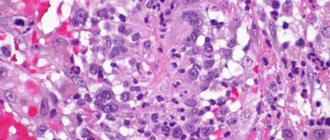

With vasculitis, multiple lesions of the lungs are visible on the fluorogram. An ENT examination reveals chronic sinusitis and otitis media (prolonged inflammation of the paranasal sinuses and inner ear). In biopsy samples of the mucous membranes, granulomatous formations, giant cells and eosinophils are found that infiltrate the tissues. A biopsy of the renal glomeruli determines the presence of ANCA in them. A simpler technique is to measure blood pressure and pulse in both arms. If these indicators are not symmetrical, this is an indirect sign of vascular damage on one side. For certain types of vasculitis, a skin and muscle biopsy is performed. To determine the degree of lung damage and decreased respiratory function, spirography is performed. In order to determine the level of blockage of blood vessels, angiography is performed - an X-ray examination of the vascular bed using contrast agents.